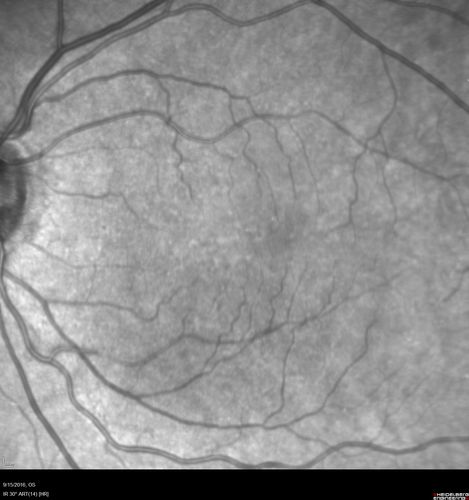

Perifoveal Microaneurysm - Not Diabetic (also reticular pseudodrusen)

87 year old female with fluctuating macular edema in the right eye from a perifoveal MA. (no treatment). VA 20/40 OU